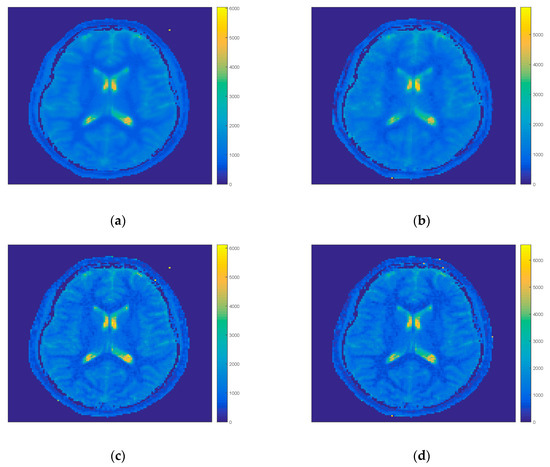

Figure 4 shows the influence of further reduction of projections on the quality of T1 maps. By decreasing the number of projections taken to the iteration process the quality of the FIR-MAP with MFM decreased, however, by considering only each sixth projection the contrast and resolution was comparable to the reference results. For IFM the spatial resolution was still better due to the way of evaluation of model for all projections. Due to that feature it was possible to decrease the time of computation of single iteration even for 9 s (for each sixth projection).

Figure 4.

T1 maps results of FIR-MAP for MFM for each projection (a), for each sixth projection (b), IFM for each projection (c) and by taking each sixth projection (d) in the iteration process for volunteer V2. The spatial resolution and image quality decreases for both initial models for each sixth projection (right column b and d) with respect to each projection (left column a and c).